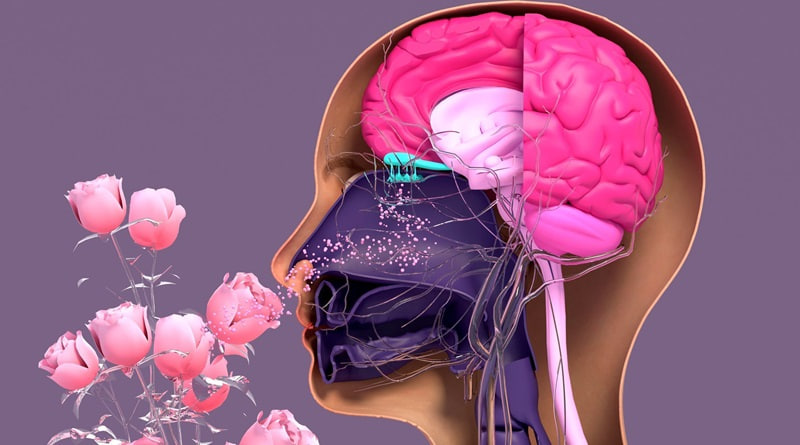

Día Internacional de la Anosmia: visibilizar la pérdida del olfato y sus implicaciones en la salud

Cada año se conmemora el Día Internacional de la Anosmia, una fecha destinada a generar…